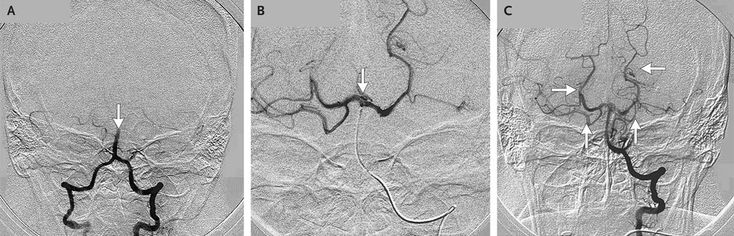

A 42-year-old woman with a history of exertional dyspnea, severe mitral stenosis (mitral valve area, 0.9 cm2) secondary to rheumatic heart disease, and atrial fibrillation was admitted for percutaneous mitral balloon valvotomy, to be performed with the MultiTrack (NuMED) single-wire, double-balloon device. After the patient underwent transseptal puncture during cardiac catheterization, consciousness became impaired, vertigo developed, and binocular visual loss occurred. We became concerned about a possible acute stroke, and cerebral angiography was performed, revealing total occlusion of the distal basilar artery, which suggested acute thrombosis (Panel A, arrow; Video 1). Selective intraarterial thrombolysis (Panel B, arrow; Video 2) was initiated 40 minutes after the ictus. Follow-up cerebral angiography was performed and showed resolution of the occlusion (Panel C, arrows; Video 3). Within 12 hours of the event, all neurologic abnormalities had resolved. The patient underwent mitral-valve replacement at a later date.